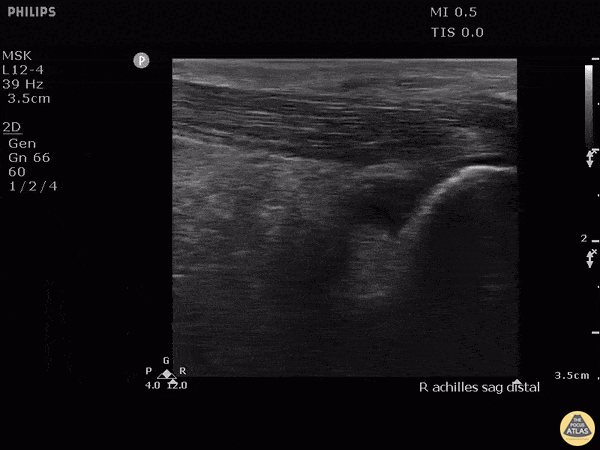

Musculoskeletal - Retrocalcaneal Bursitis

Hockey player with progressive posterior ankle/heel pain. Felt sudden worsening while skating. Clip shown reveals retrocalcaneal bursitis along with insertional Achilles tendinopathy. Image courtesy of Robert Jones DO, FACEP @RJonesSonoEM Director, Emergency Ultrasound; MetroHealth Medical Center; Professor, Case Western Reserve Medical School, Cleveland, OH View his original post here